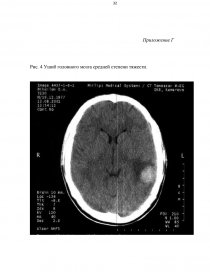

ПРИЛОЖЕНИЯ…………………………………………………………………..28